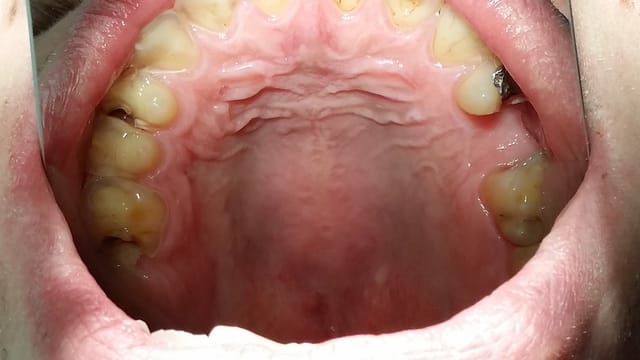

Nouveau patient ,sympa, 28 ans, assez motivé. paro ok, occlusion classe 1 , rien de problématique en soit, pas plus stressé que soit mais voila, le monsieur est légèrement bruxomane, voir les photos ci jointes ( désolé, photos prises avec le téléphone). On ne lui a jamais parlé de sa bruxomanie et encore moins de gouttière occlusale bien qu'il soit assez assidu dans ses ddv de contrôle.

douleurs assez fortes intermittentes au chaud/froid. Il a vu rapidement un confrère qui lui a parlé des DDs à extraires, elles sont il est vrai sorti horizontalement, mais pour moi ce sont surtout les caries en 16-14 et 24 26 qui en sont à l'origine. Pour ca pas de problème , mais c'est l'état de perte de substance des secteurs cuspidés qui fait peur...pas de douleur sur ces dents d'ailleurs, mais le patient voit bien qu'il y a un problème.

Secteur occlusal maxillaire jcdzni - Eugenol

reflux gastrique, diète acide? semble voir érosion des cuspides palatines des prémolaires supérieures?